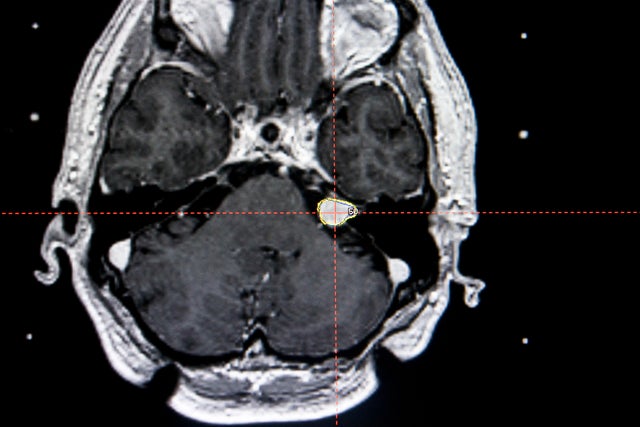

29. Benign tumors

This scan shows a benign brain tumor on the auditory nerve.